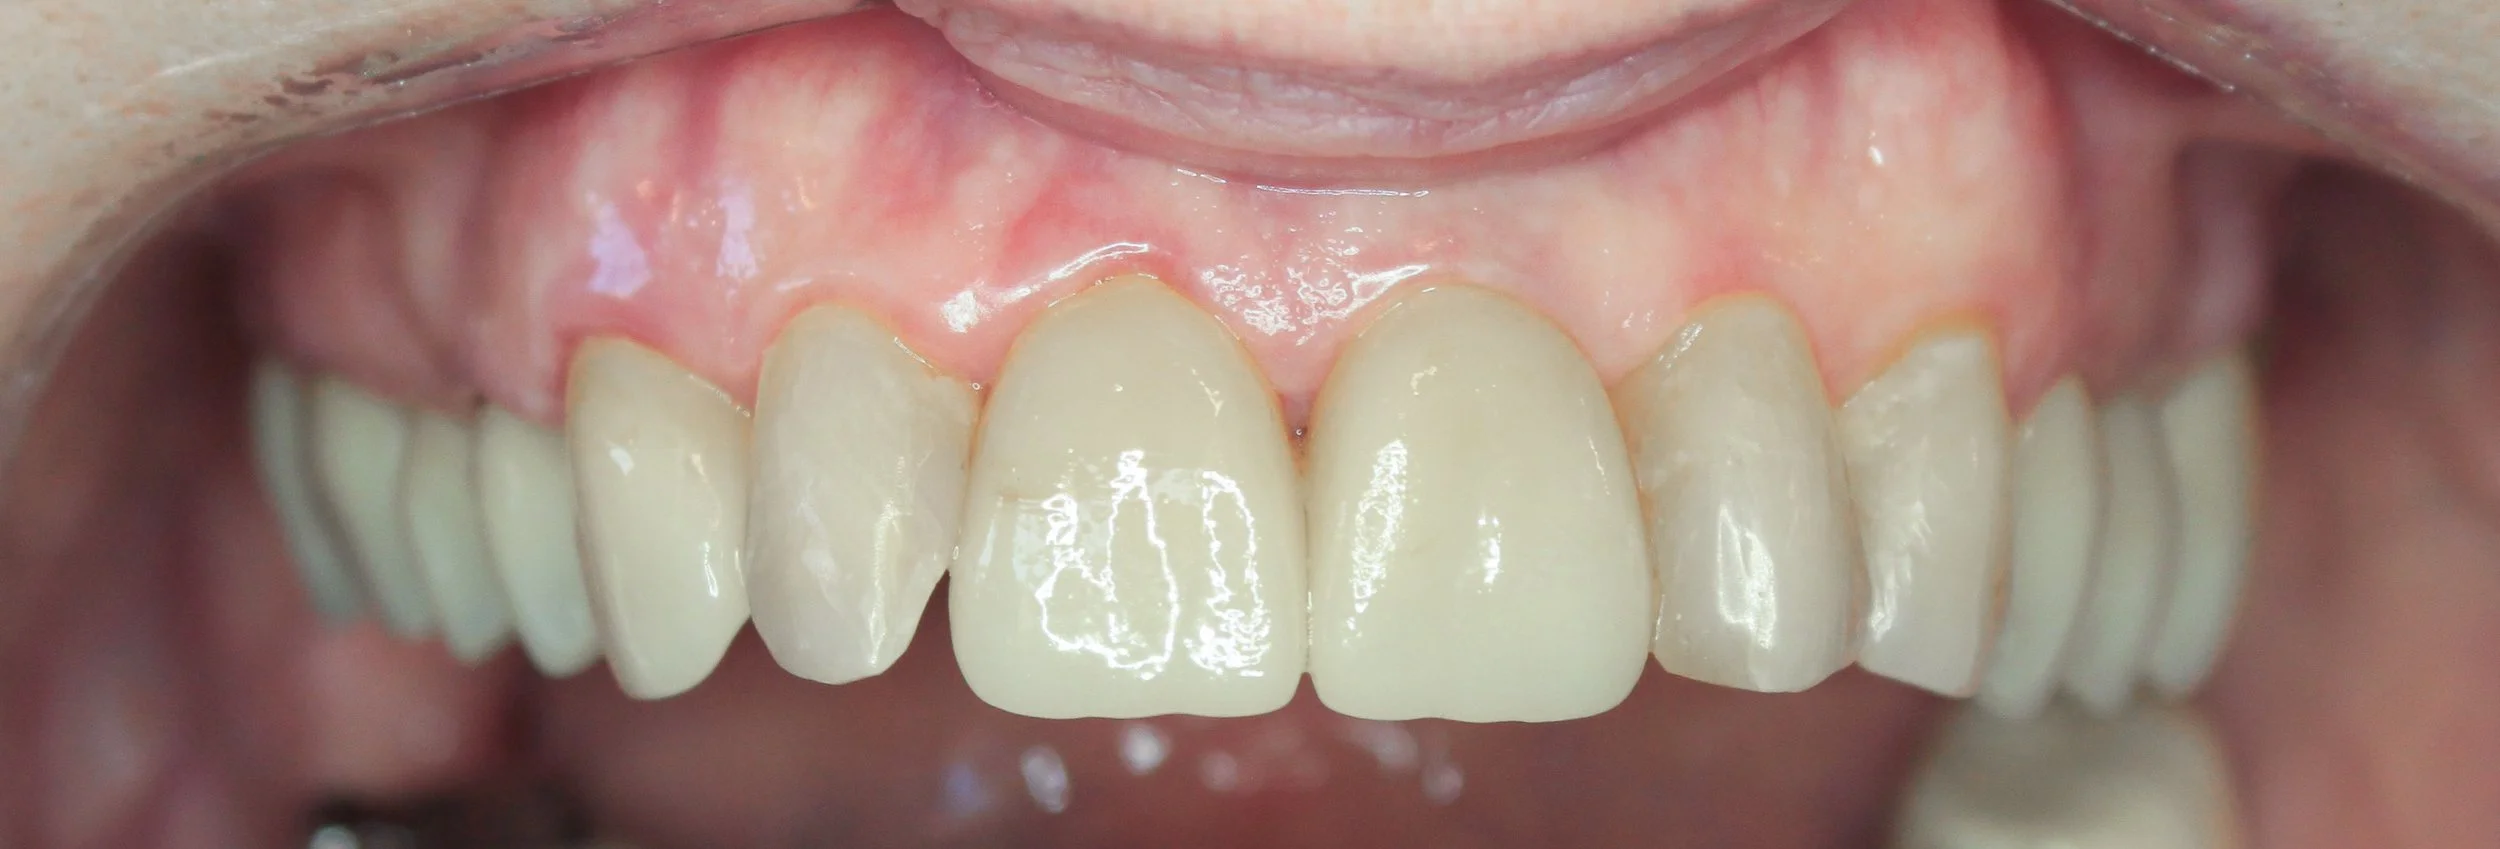

AVANT / APRÈS